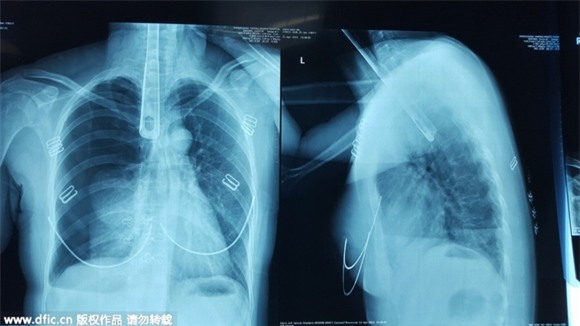

Người phụ nữ ban đầu đã cố gắng dùng ngón tay để 'móc họng', tiếp theo là dùng đũa, nhưng tất cả đều không có hiệu lực. Cuối cùng, cô đặt một thìa kim loại trực tiếp vào miệng và thông nó sâu xuống thực quản. Chiếc thìa sắt dài khoảng 30cm.

Rất may, sự việc đã được con gái của người phụ nữ này phát hiện và đưa đến bệnh viện cấp cứu.